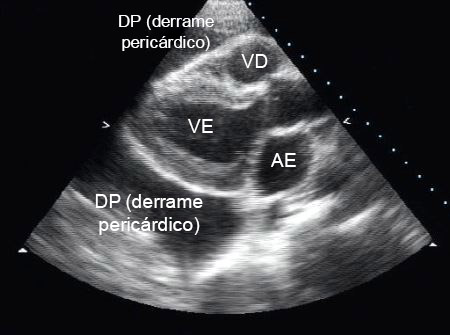

A ecocardiografia transtorácica é a investigação de escolha para suspeita de derrame pericárdico. Trata-se de uma modalidade diagnóstica não invasiva e eficaz. Além de confirmar o diagnóstico, a ecocardiografia permite ao operador avaliar o tamanho e os efeitos hemodinâmicos do derrame.[7]

Um espaço sem eco entre as duas camadas do pericárdio indica a presença de derrame.[Figure caption and citation for the preceding image starts]: Incidência do eixo paraesternal longitudinal de um derrame pericárdico (DP); AE = átrio esquerdo, VE = ventrículo esquerdo, VD = ventrículo direitoDo acervo do Dr. Rajdeep Khattar [Citation ends].

[Figure caption and citation for the preceding image starts]: Incidência apical das 4 câmaras de um ecocardiograma bidimensional de um paciente com derrame pericárdico tuberculoso; AE = átrio esquerdo, VE = ventrículo esquerdo, DP = derrame pericárdico; AD = átrio direito, VD = ventrículo direitoDe: George S, Salama AL, Uthaman B, et al. Heart. 2004; 90:1338-1339 [Citation ends].

A avaliação ecocardiográfica geral do derrame pericárdico inclui:

Tamanho

A espessura máxima do derrame diastólico final (distância entre as camadas epicárdica e parietal do pericárdio) é medida e o tamanho do derrame é classificado como:

Trivial (visto apenas na sístole)

Pequeno (<10 mm)

Moderado (10-20 mm)

Grande (>20 mm)

Muito grande (>25 mm)

Localização

Circunferencial

Loculado

Consistência

Limpo

Parcialmente organizado (com fios que abrangem as duas camadas do pericárdio)

Totalmente organizado.